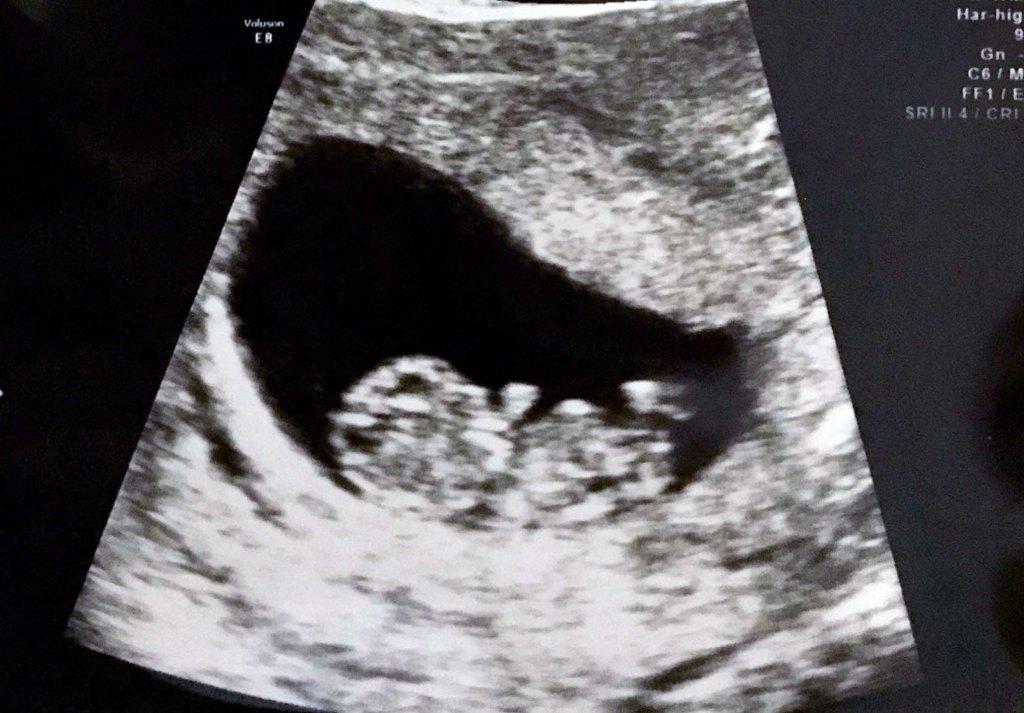

I do not know when the spirit enters the body in the womb. I do know I could see my little one twisting and wiggling on both 2D and 3D ultrasounds at 11 weeks (first trimester), and then the ultrasounds at 20 weeks (halfway through pregnancy) showed even more of her clearly human body, active and curious. Now, I feel her every day, playing, pushing, and punching away at my insides (making me need to pee all the time!).